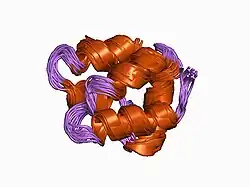

Annexin A1 belongs to the annexin family of Ca2+-dependent phospholipid-binding proteins that have a molecular weight of approximately 35,000 to 40,000 Dalton and are preferentially located on the cytosolic face of the plasma membrane. Annexin A1 protein has an apparent relative molecular mass of 40 kDa with phospholipase A2 inhibitory activity.[6]

- Weng X, Luecke H, Song IS, Kang DS, Kim SH, Huber R (March 1993). "Crystal structure of human annexin I at 2.5 A resolution". Protein Science. 2 (3): 448–458. doi:10.1002/pro.5560020317. PMC 2142391. PMID 8453382.